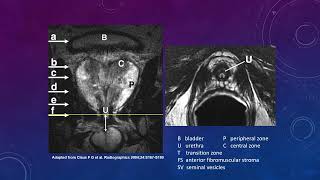

Introduction to PI-RADS Prostate MRI Introduction

Prostate MRI Introduction Multi-parametric Prostate MRI using PI-RADS v 2.1: an Introduction

Multi-parametric Prostate MRI using PI-RADS v 2.1: an Introduction Prostate MRI: Introduction PI-RADS v2.1 on MRI